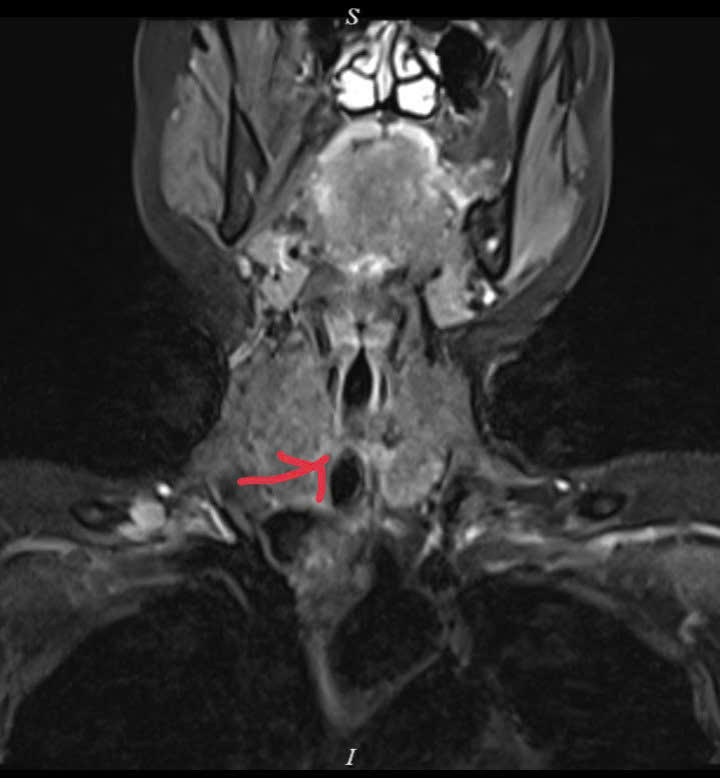

Trước đó, bà Đ.T.T nhập viện trong tình trạng khó thở kéo dài, thở khò khè nhiều tháng nhưng chưa xác định được nguyên nhân. Sau khi tiếp nhận, các bác sĩ Trung tâm Ung bướu (Bệnh viện C Đà Nẵng), với sự chỉ đạo của BSCKII Võ Trung Nghĩa (Giám đốc Trung tâm) đã đánh giá toàn diện, chỉ định các phương tiện chẩn đoán chuyên sâu và phát hiện khối u nằm trong khí quản.

Khối u nằm sát thanh quản, ngay đoạn trên của khí quản, khiến việc điều trị đặc biệt phức tạp. Đây là vùng giải phẫu hẹp, tập trung nhiều cấu trúc quan trọng liên quan đến hô hấp, phát âm và nuốt, vị trí này rất nguy hiểm vì chỉ cần bít tắc thêm một phần nhỏ cũng có thể đe dọa tính mạng.